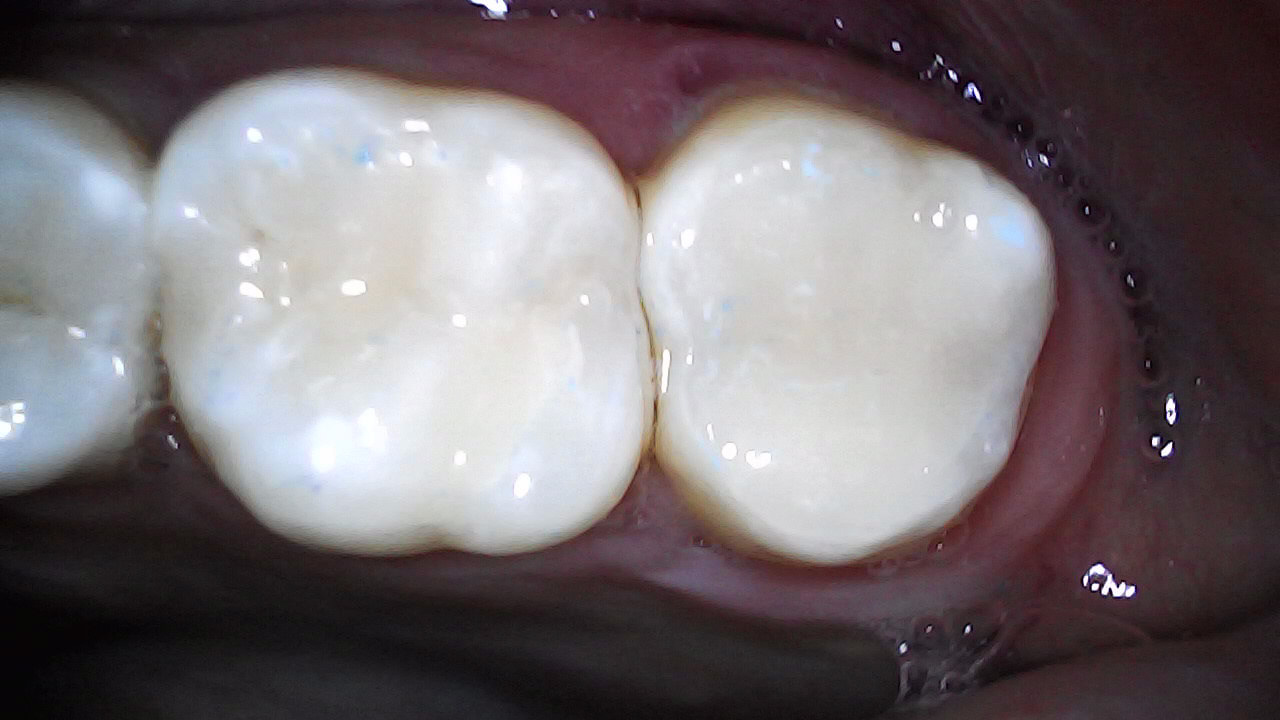

Initial